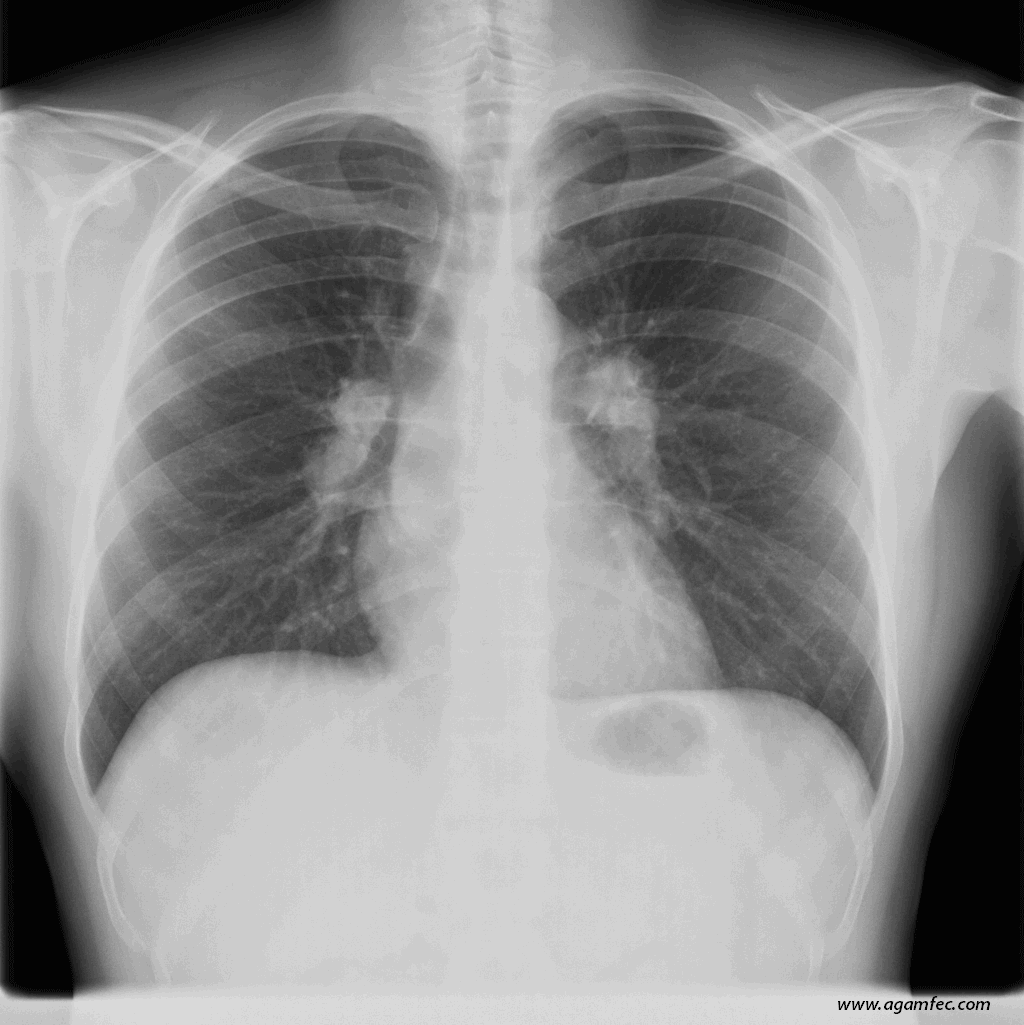

Figura 1. Radiografía de tórax PA y lateral de paciente con Eritema Nodoso, en la que se observan adenopatías hiliares bilaterales, sugestivas de Sarcoidosis